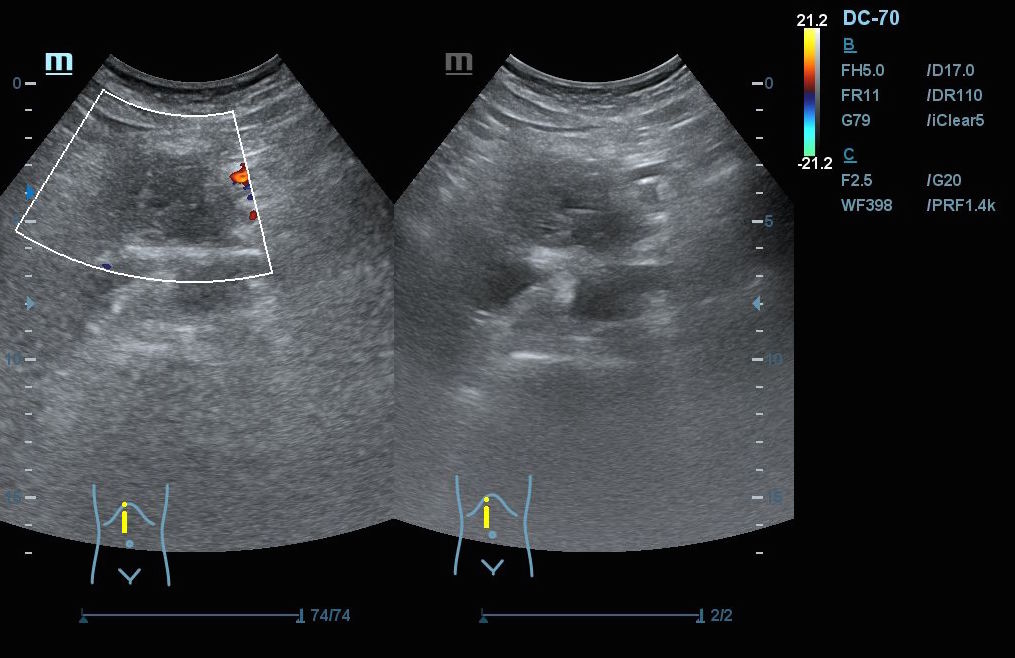

Hallazgos ecográficos: En el epigastrio se observa una imagen anecoica tubular, sin captación en Doppler, con un diámetro mayor a 2 cm, que sugiere una dilatación del colédoco (imagen 1). La vesícula biliar se encuentra completamente distendida y hepatizada, con una imagen en «doble cañón de escopeta» sugestiva de colestasis (imagen 2). En los cortes longitudinales se identifica una masa anterior a la aorta en el corte paramedial izquierdo, aparentemente localizada en el cuerpo del páncreas (imagen 3). En los cortes transversales se observa una masa que afecta tanto al cuerpo como a la cabeza del páncreas (imagen 4).